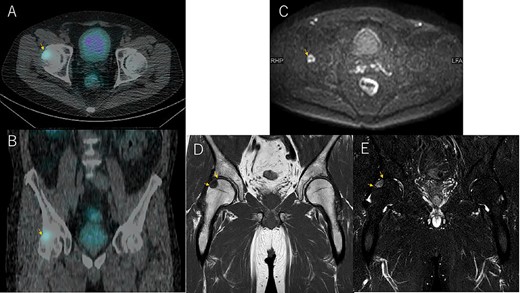

Bone mineral density (g/cm3) of the lumbar spine, right femoral neck and left femoral neck was 1.017, 0.952 and 0.750, respectively, with T-score of −0.2, −0.1 and − 0.9 and young adult mean of 97, 99 and 87, respectively. Somatostatin receptor scintigraphy showed an accumulation in the right femoral head (Fig. 2A and B), and magnetic resonance imaging showed a well-defined 14 × 16 × 17 mm borderline mass on the proximal lateral side of the right femoral head with low signal on T1-weighted images and high STIR signal on diffusion restriction (Fig. 2C–E). Venous sampling was then performed, revealing an elevated FGF23 concentration in the right medial femoral circumflex vein. Based on the above, a diagnosis of TIO in the right femoral head was made as the underlying cause of FGF23-related hypophosphatemic osteomalacia.

Somatostatin receptor scintigraphy shows a pale accumulation at 24 h (A and B). MRI diffusion-weighted images show a high-signal change in axial (C) consistent with the accumulation site (A). T1-weighted images (D) and STIR (E) in coronal.